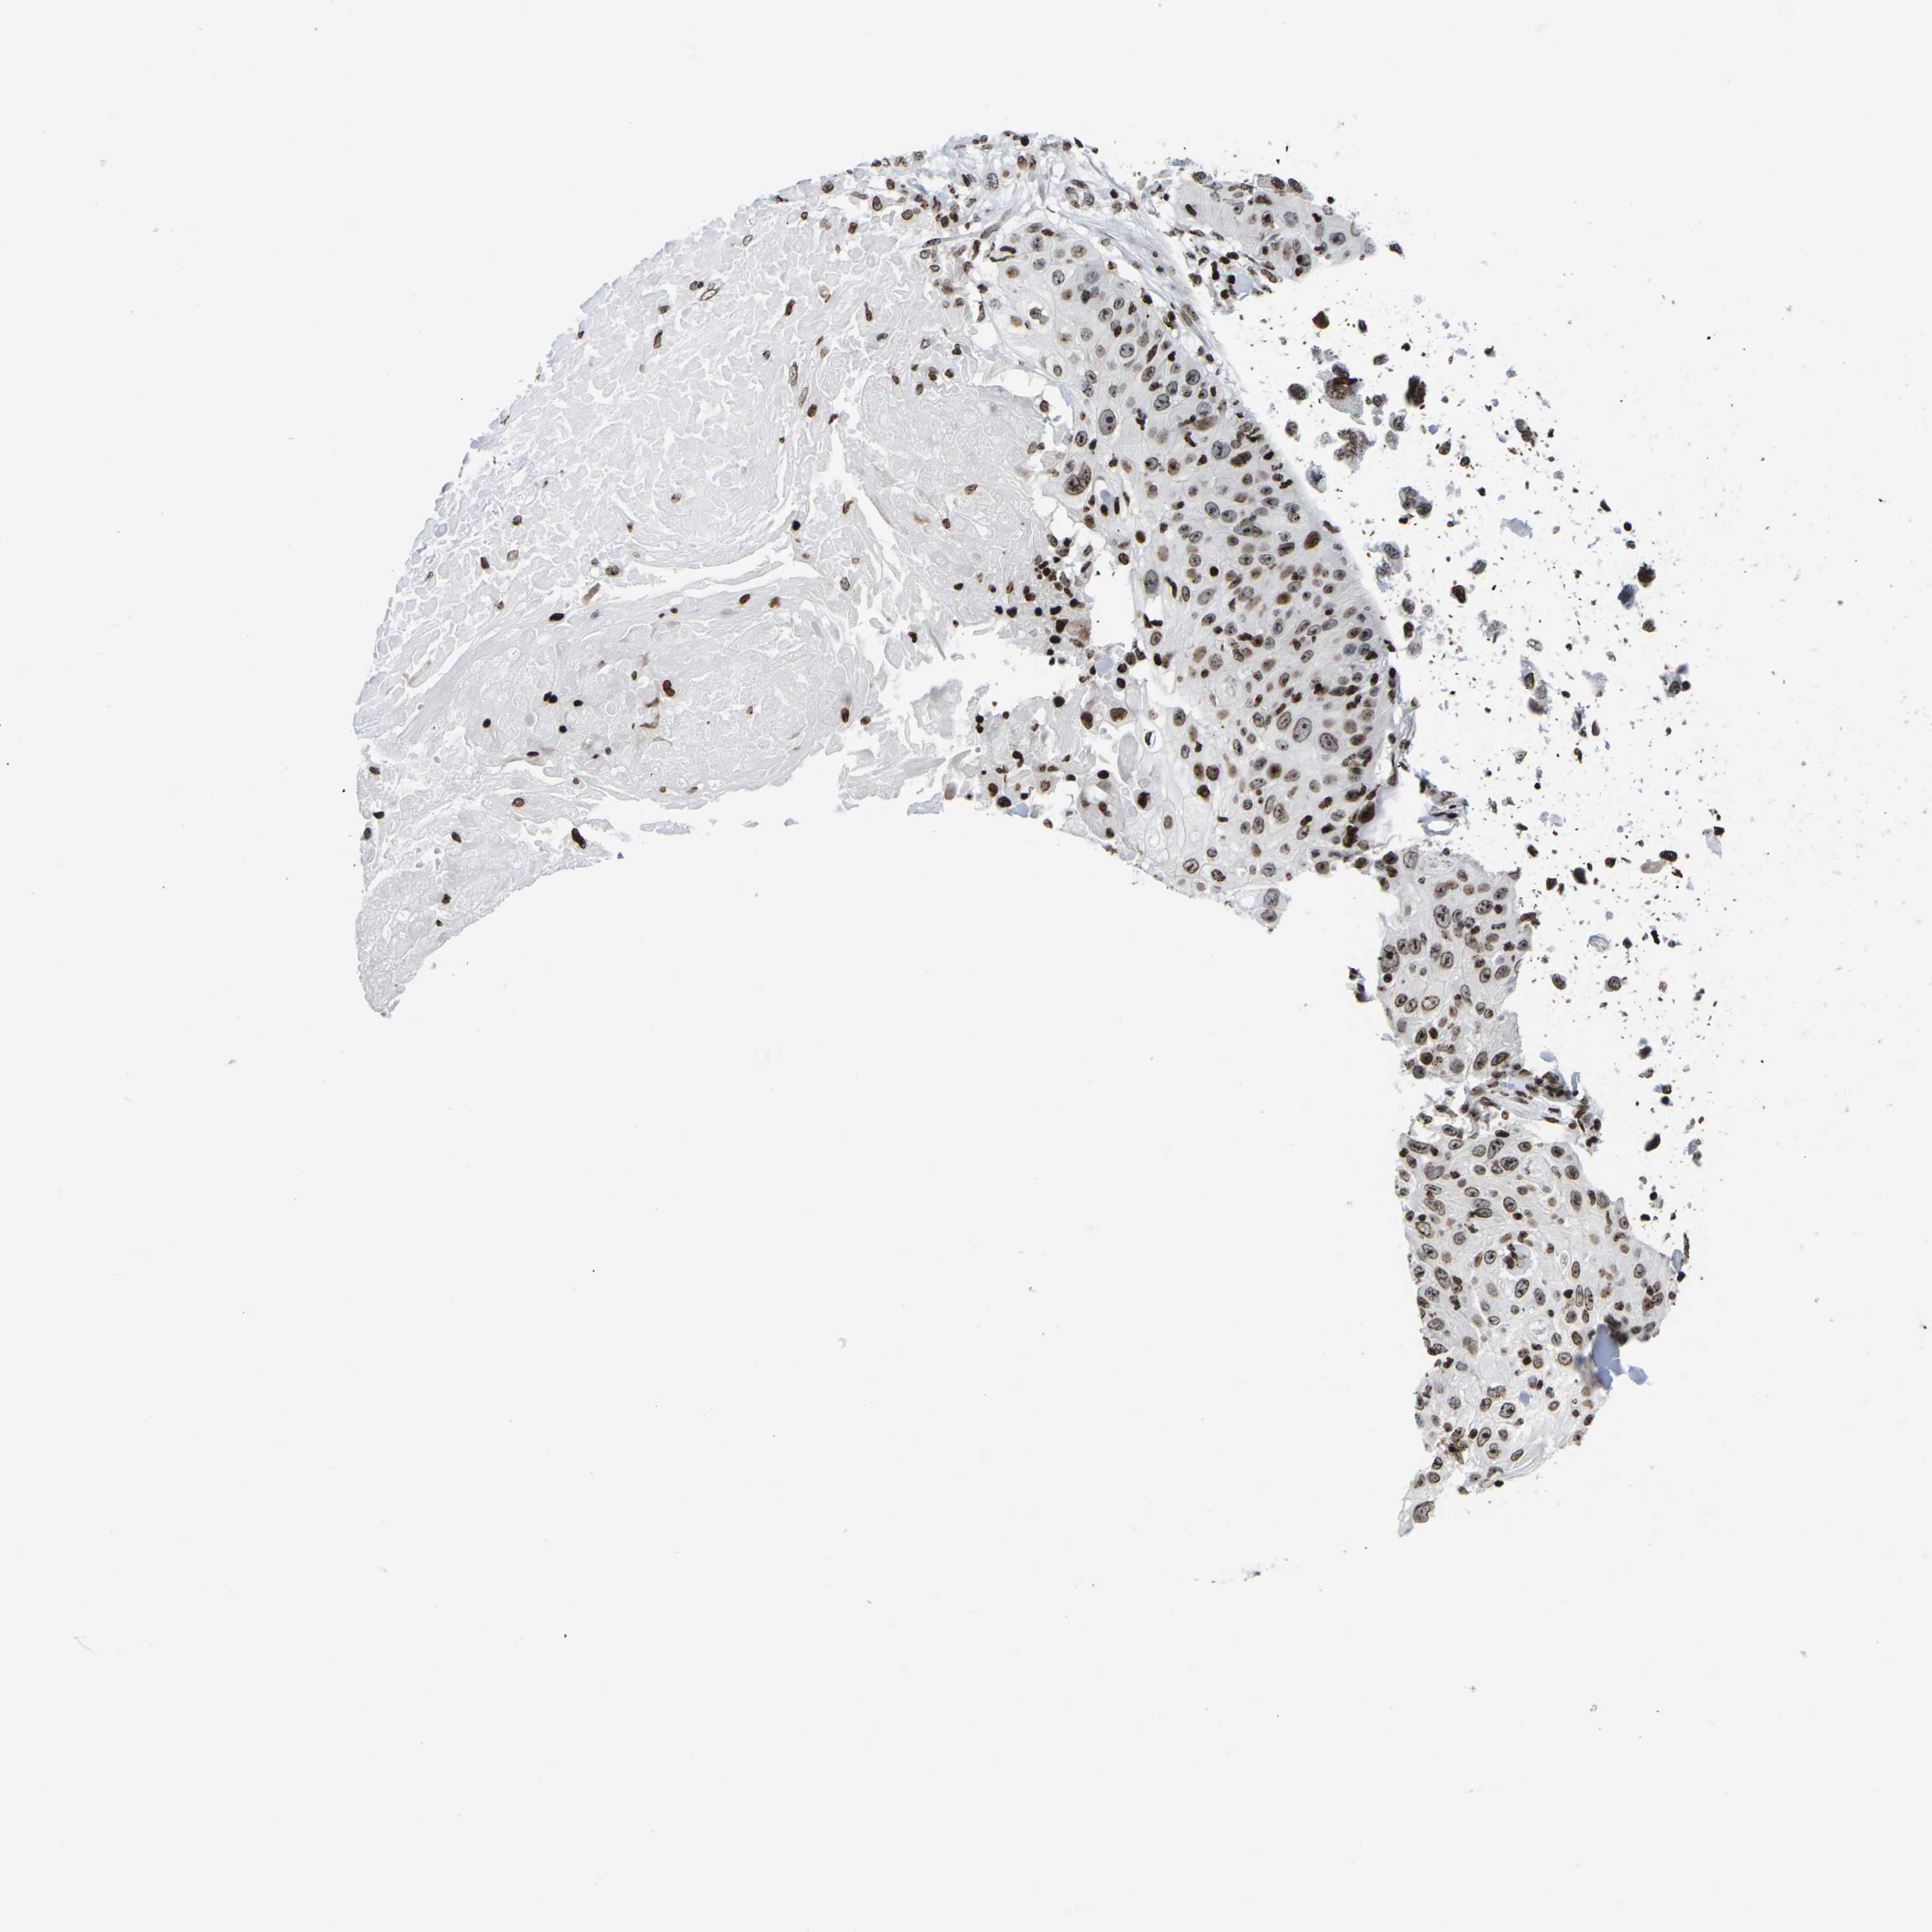

SKIN CANCER - Protein expressioni

A mouse-over function shows sample information and annotation data. Click on an image to view it in a full screen mode. Samples can be filtered based on level of antibody staining by selecting one or several of the following categories: high, medium, low and not detected. The assay and annotation is described here.

Each image is clickable and will lead to virtual microscopy that enables deeper exploration of all samples and also displays staining intensity scores, fraction scores and subcellular localization as well as patient and tissue information for each sample.

Antibody HPA055907

Basal cell carcinoma

Squamous cell carcinoma, NOS

Squamous cell carcinoma, metastatic, NOS

Squamous cell carcinoma in situ, NOS

Adnexal tumor, benign